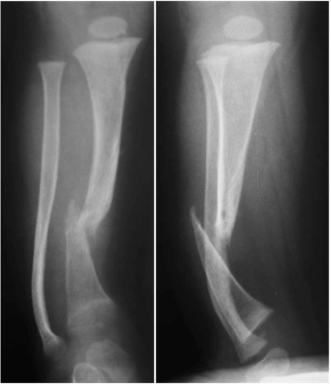

El tratamiento de la Pseudoartrosis Congénita de Tibia y Peroné (PCTyP) ha sido diverso. Todas las técnicas de tratamiento tienen una cuota de complicaciones, pero es la re-fractura y la falta de unión las principales consecuencias que se desean evitar. El objetivo de esta investigación se basa en analizar las técnicas quirúrgicas empleadas en nuestro centro y determinar los resultados. Se realizó un estudio retrospectivo, donde se estudiaron 11 pacientes con esta enfermedad con un seguimiento promedio de 4,73 años (DS±4,56). Todos los pacientes en quienes se utilizó la técnica de Charnley-Williams (CW) lograron la consolidación, la protección del clavo funcionó hasta que el extremo proximal de la tibia queda desprotegido al crecer el hueso y se produjeron angulaciones en esta zona, usualmente en la tibia proximal. Con el uso del clavo endomedular (EM) telescópico de Fassier-Duval (FD) se logra la protección de todo el hueso, inclusive durante el crecimiento. Se concluye que la técnica de CW es un buen método para la resolución de esta enfermedad y con el uso del clavo EM de FD se evita la refractura y se logra la unión permanente a medida que continúa el crecimiento del hueso. La discrepancia de los miembros inferiores es debida a la afectación de la tibia que compromete su crecimiento normal.